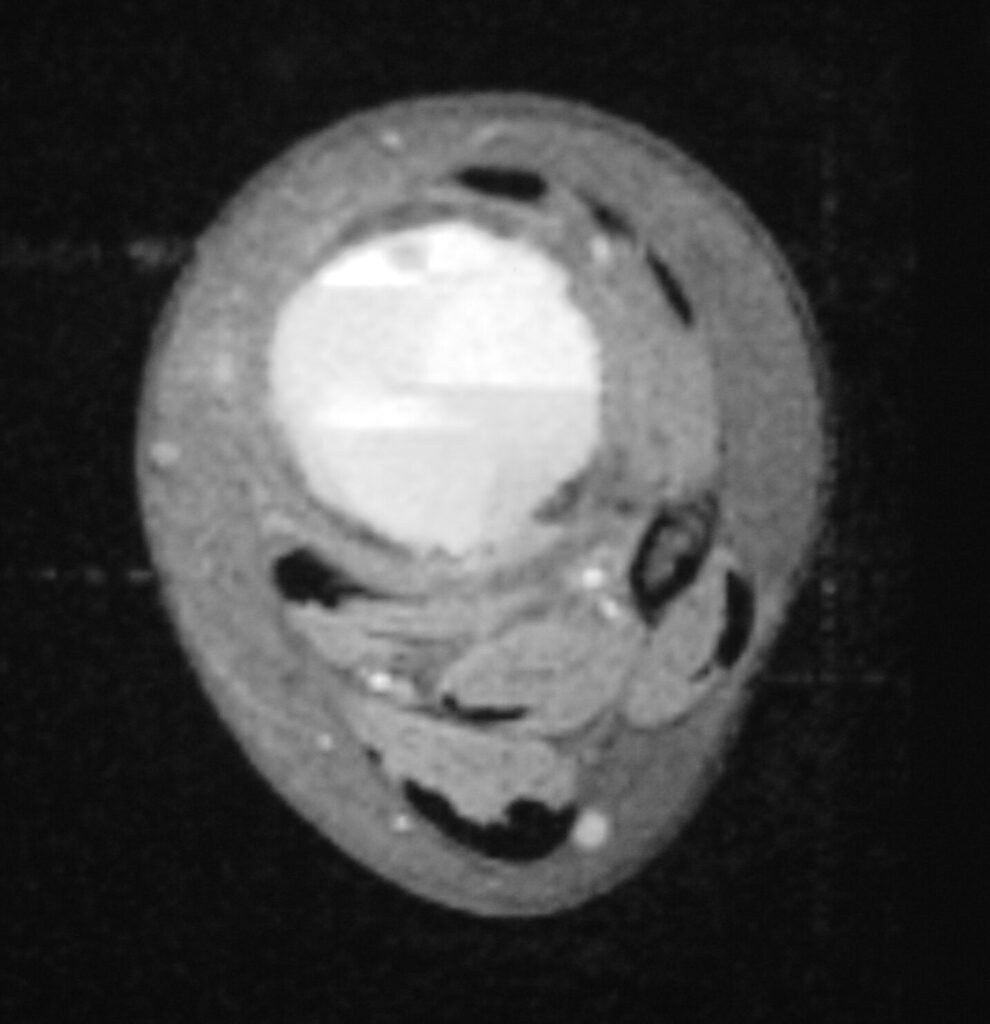

Fig 2 a-e. MRI of an ABC of Distal Tibia: Fig 2 a-c: geographic cystic expansile lesion with fluid-fluid levels. The fluid-fluid levels are caused by bleeding into the cavities. The blood collects and the degredation products settle to the gravity dependent areas of the cavities. This shows up as fluid-fluid levels on the MRI. Fig 2 d,e: This is a gadolinium enhanced MRI of the ABC of the distal tibia. There is peripheral and septal enhancement indication cyst formation. The contrast outlines the cystic cavities but does not enter into the center

Fig 2c: Axial T2 weighted MRI of an ABC